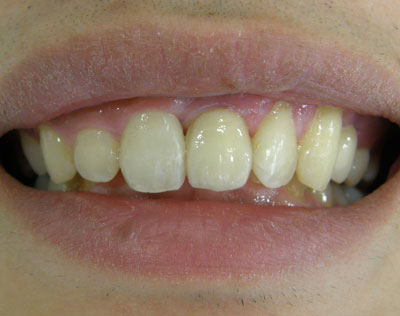

| Before | After |